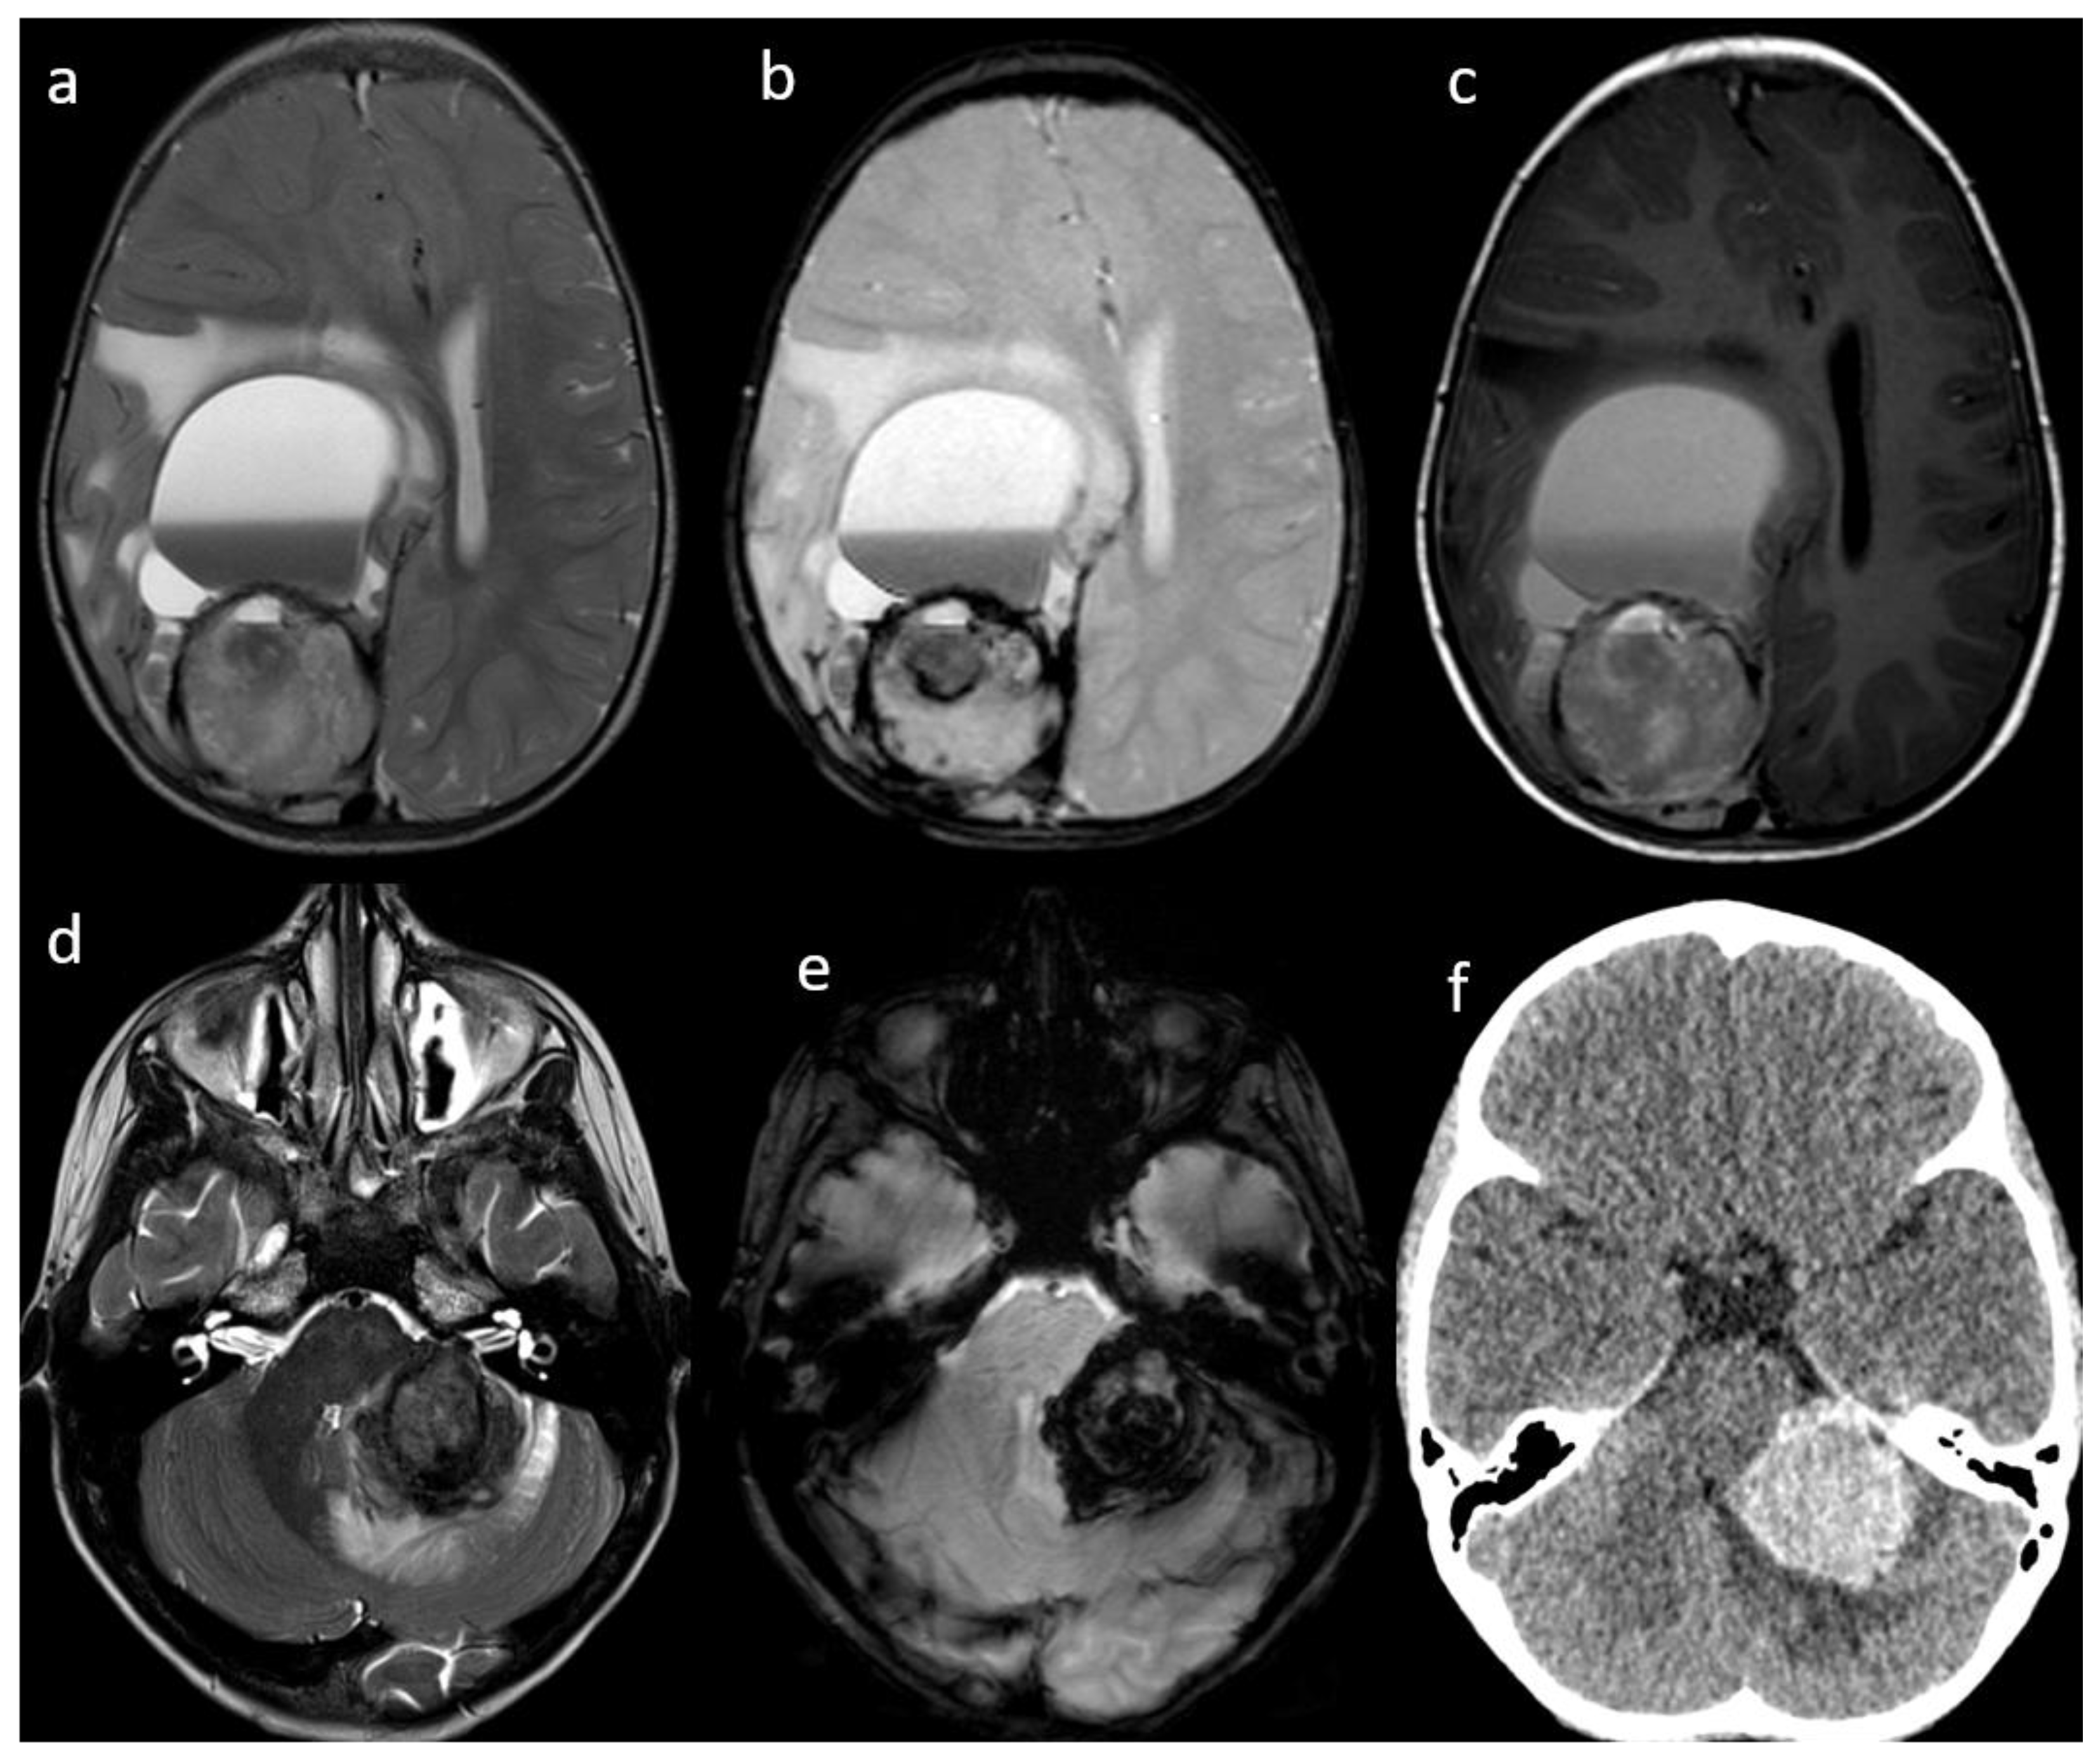

Central Nervous System Tumors 裁断済み WHO Classification of Tumours, 5th ed., Vol.6 Centralの詳細情報

WHO Classification of Tumours, 5th ed., Vol.6 Central。Central Nervous System Metastasis in Neuroblastoma: From。Amazon | Who Classification of Tumours of the Central。Central Nervous System Tumors2021年に改訂されたwho脳腫瘍分類の大元です。最新版です。4つに分けて裁断したため、多少紙の大きさが違いますが、文字切れはないと思います。裁断済みです。ご理解の上ご購入下さい。。DICER1-associated central nervous system sarcoma with neural。カラー版 国際診療のための内科アトラス大事典。しなやかで強い鉄鋼材料 革新的構造用金属材料の開発最前線*。クラウンブリッジの臨床 第5版。歯科再生・修復医療と材料